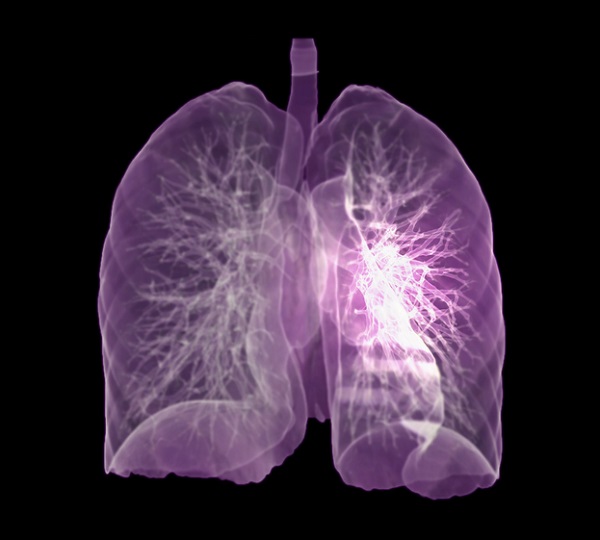

호흡 곤란은 폐암의 증상입니다. 폐암 환자의 약 4분의 1이 호흡곤란 증상을 보이며, 이는 다발성 폐 전이가 양측 증상을 나타내거나 악성 흉막삼출이 폐암과 함께 발생할 때 발생합니다. 폐암은 점차 흉통을 악화시킬 수 있으며, 폐암이 진행됨에 따라 폐암의 크기가 커지거나 그 부위에 물이 차게 되면 호흡이 흉막을 자극하여 호흡곤란과 흉통을 유발할 수 있습니다. 격렬한 작업이나 격렬한 운동을 하지 않았더라도 호흡곤란이 발생하거나 호흡이 불편한 경우 의사의 진찰을 받는 것이 좋습니다.

폐암의 초기증상 중에 흉통이 있습니다. 폐암 환자의 약 1/3이 흉통을 호소합니다. 흉통의 원인은 폐 가장자리에 종양이 형성되어 암세포를 생성하고 흉벽과 흉막에 침착되어 통증을 유발하는 것입니다.

흉통의 원인은 여러 가지가 있을 수 있지만, 오늘날 우리가 다루고 있는 폐암으로 인한 흉통은 경미한 통증보다는 지속적인 따끔거림과 둔한 통증을 동반한다는 점에 유의하시기 바랍니다. 또한 암은 흉막이나 흉벽 대신 갈비뼈로 퍼져 통증을 유발할 수 있습니다. 종양은 주변 조직 세포를 자극할 수 있으므로 계속해서 통증을 유발하는 경우 의사의 진찰을 받는 것이 좋습니다.